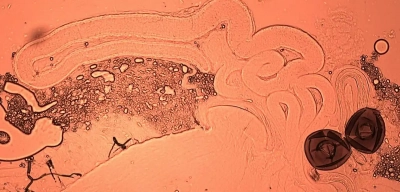

Espermatozoides marcados con proteína fluorescente verde en la espermateca de una mosca de la fruta. Krish Sanghvi

Espermatozoides marcados con proteína fluorescente verde en los testículos y las vesículas seminales de una mosca de la fruta macho. / Krish Sanghvi